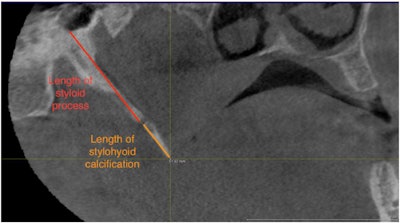

Cone-beam computed tomography (CBCT) scans showed that root canal treatments were significantly linked to stylohyoid ligament calcification, and the association was independent of other predisposing factors. This is believed to be the first reported study showing an association between SHL calcifications and root canals, the authors wrote.

Since dental diseases occur near SHLs, the authors explored the potential associations between intraoral signs of odontogenic inflammatory events and SHL calcifications. Using CBCT scans from 175 patients, they retrospectively assessed the frequency of dental extractions, root canals, periapical lesions, and furcation lesions, according to the study.

Calcified SHLs were detected on the right side of 71 patients (41%) and the left side of 58 patients (33%). Of patients with SHL calcification, 14% reported having tonsillectomies and 10% reported trauma, the authors wrote.